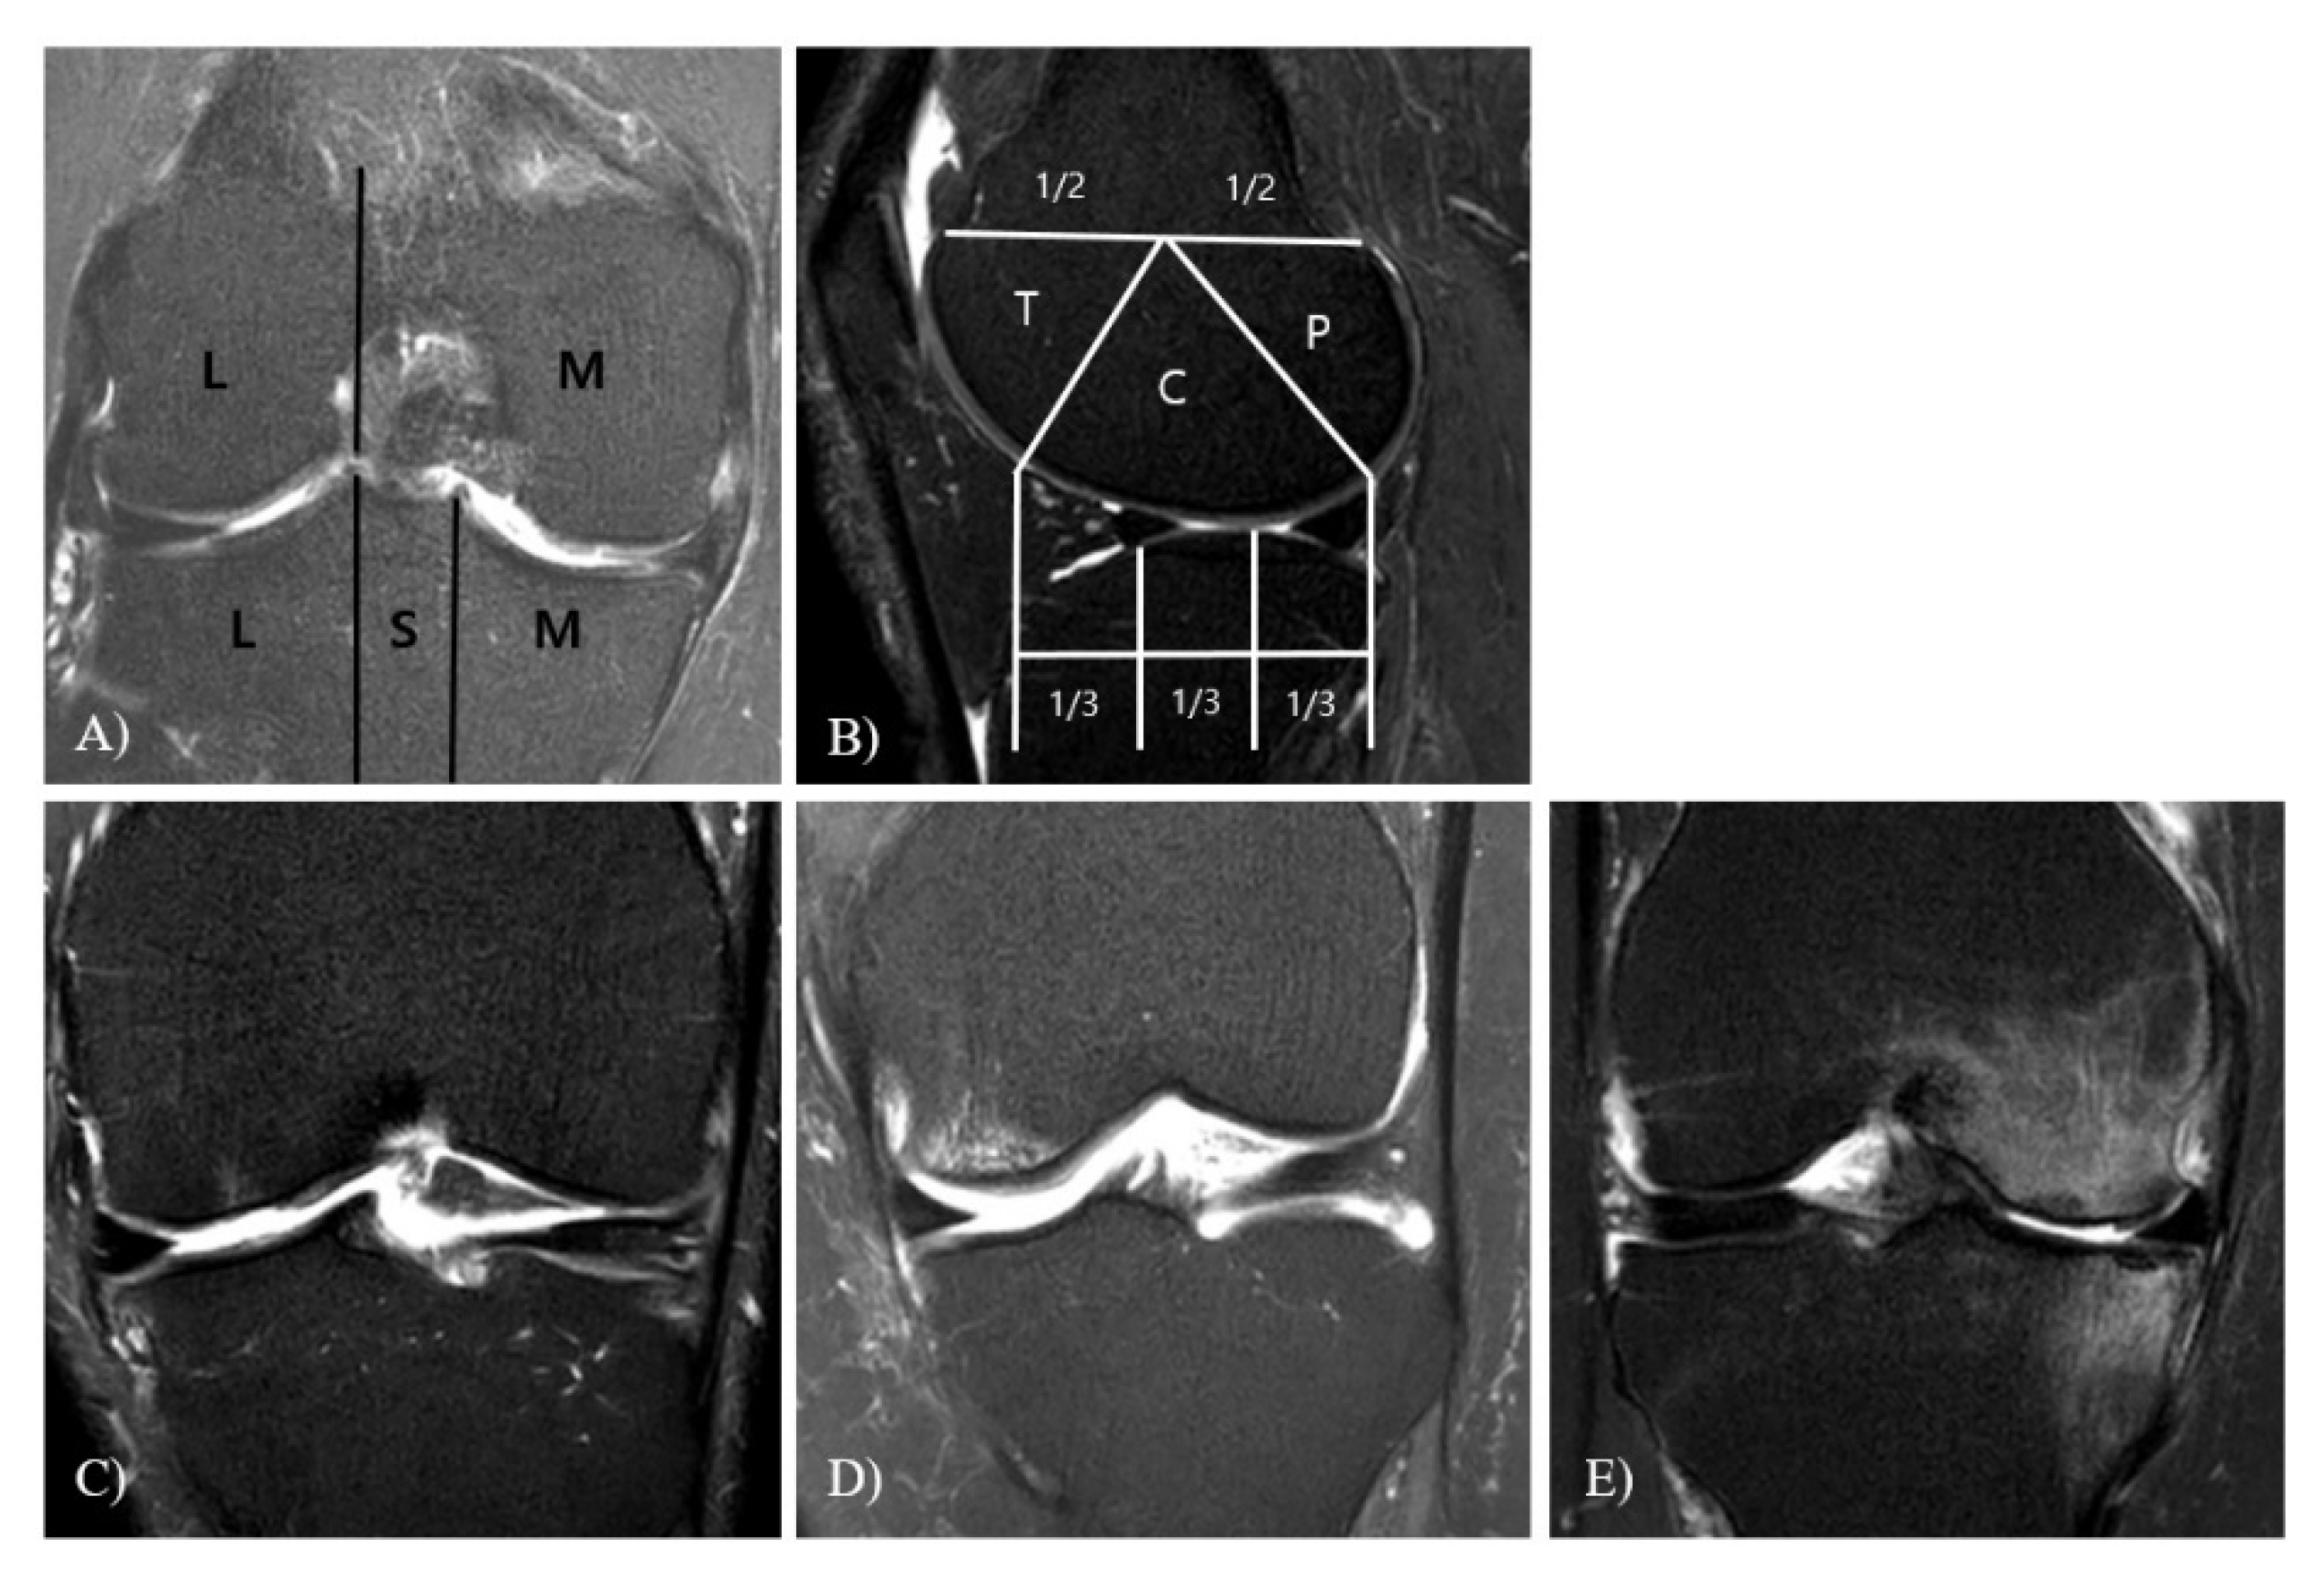

WBL

TVA

MOAKS

Meniscal Extrusion